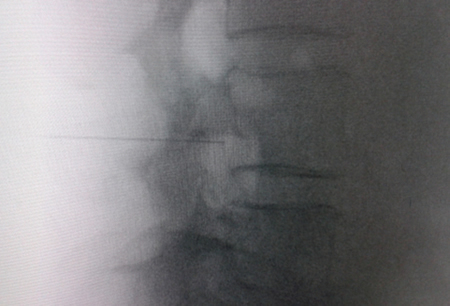

Figure 1

Figure 2